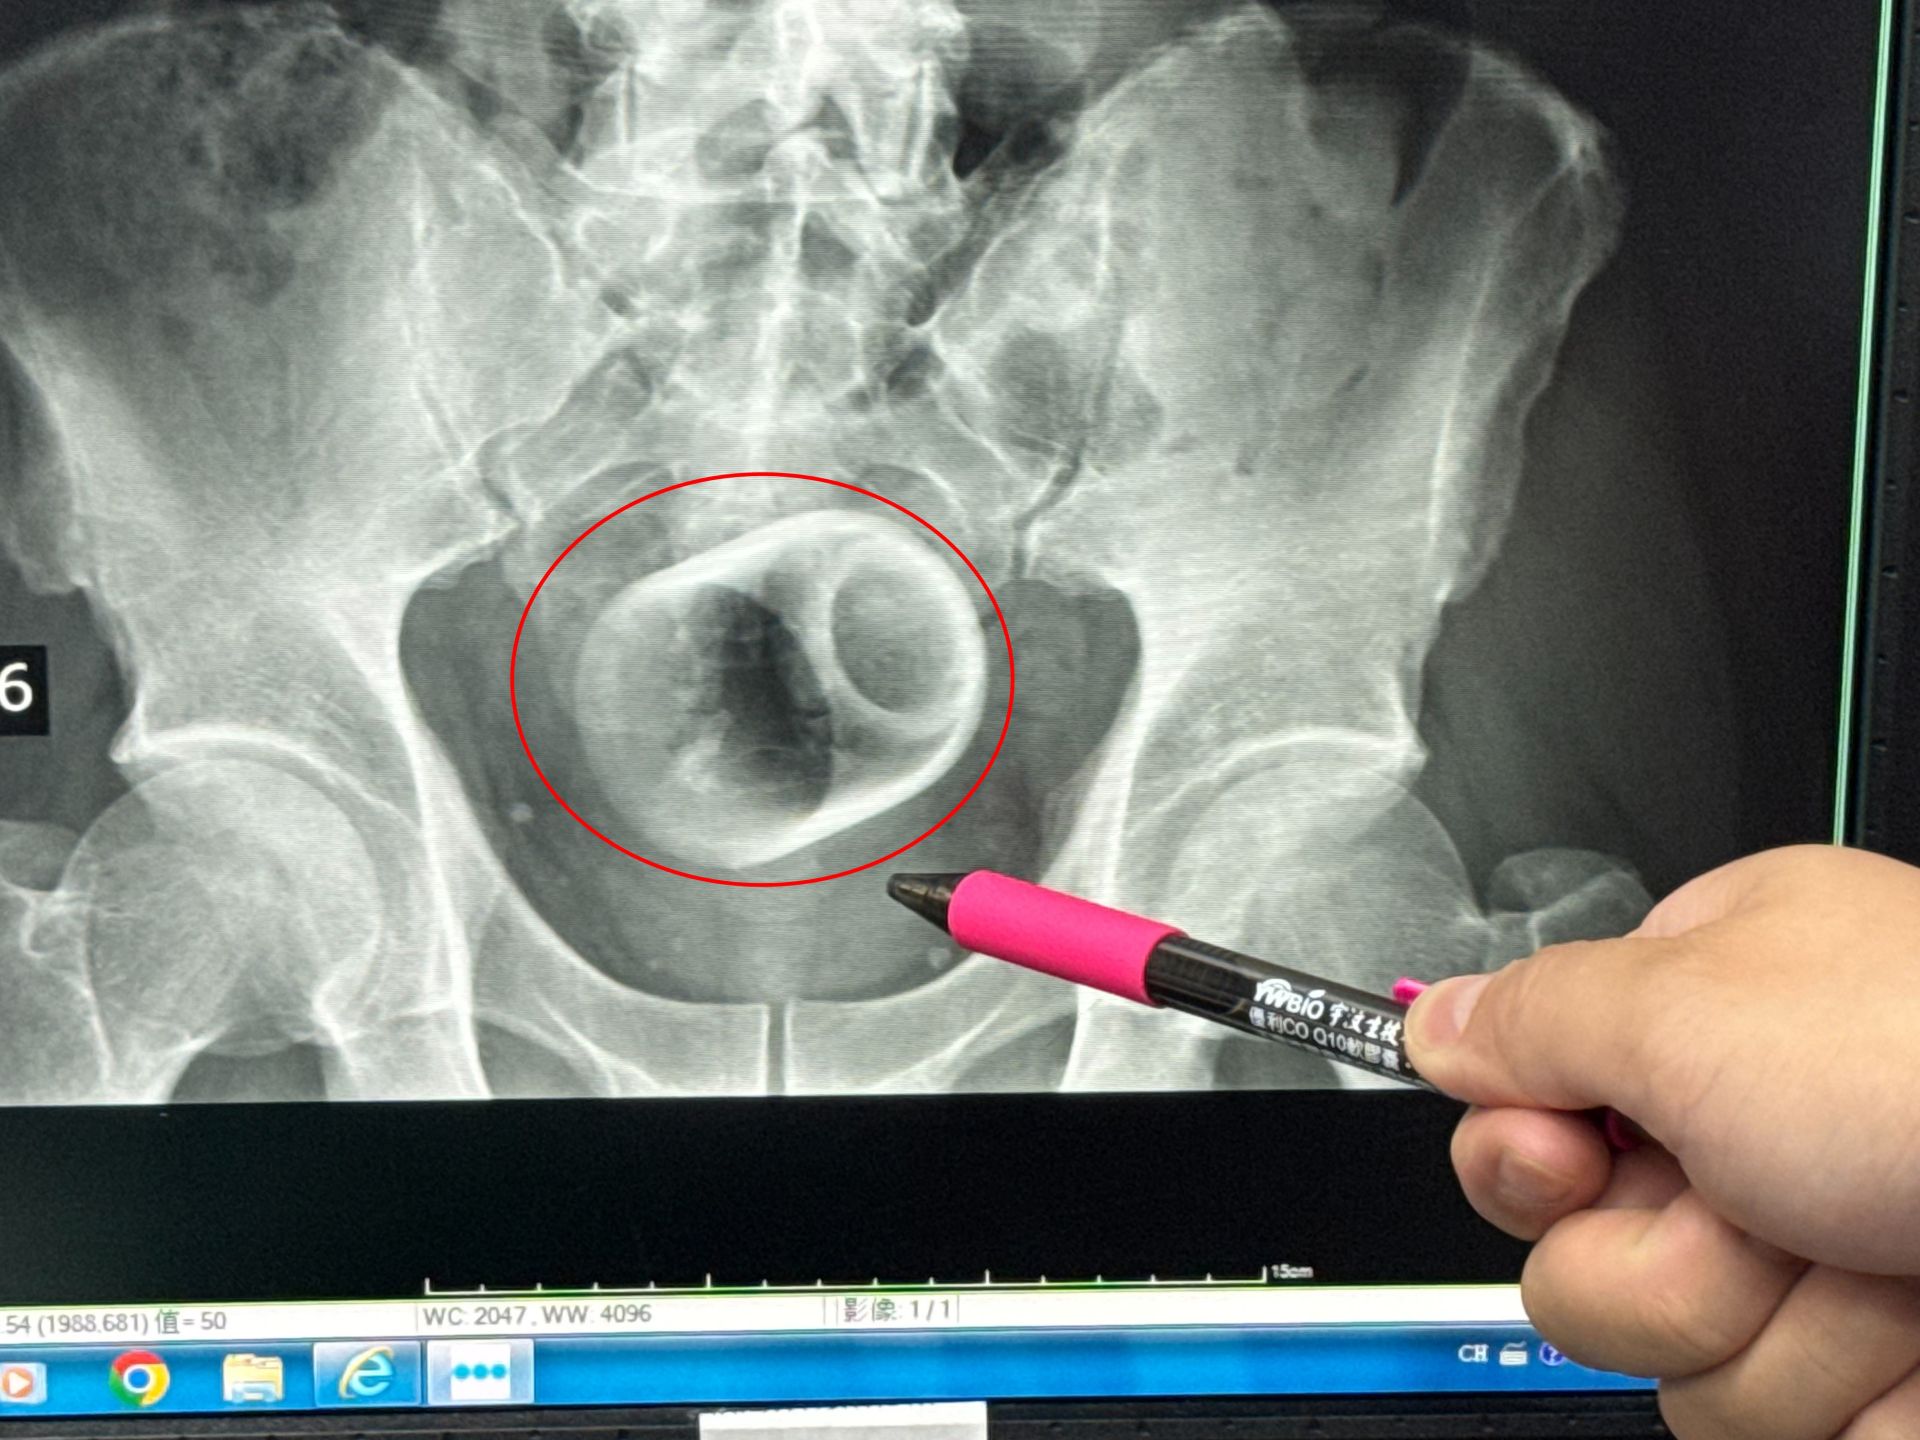

一名男子把陶瓷杯塞進肛門,X光片顯示出杯子放在骨盆腔內,經手術後才取出。大甲李綜合醫院提供

駐診在李綜合醫院的台中榮總外科醫師吳坤達表示,該名患者到院時,自訴三天無法大便非常困擾,害羞不敢提及自己肛門塞了一個杯子,經過X光攝影,看到骨盆腔內有一個杯子,杯口朝下,因此,馬上安排進手術室,要把杯子拿出來。